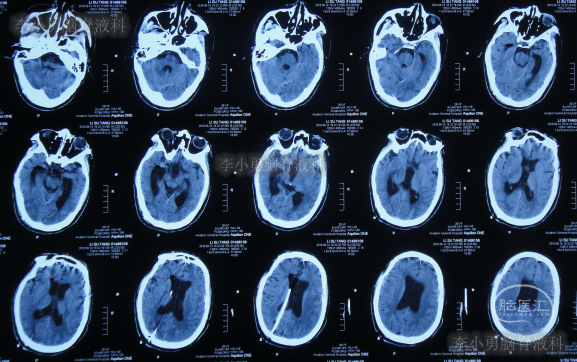

但按癫痫治疗2天后仍无明显改善,家属考虑还是跟脑积水有关,于2016年4月6日第5次返回第三家的给予手术的某三甲医院,查头颅MRI(图-5)和全身检查后认为没有明显异常,给予下调分流泵。